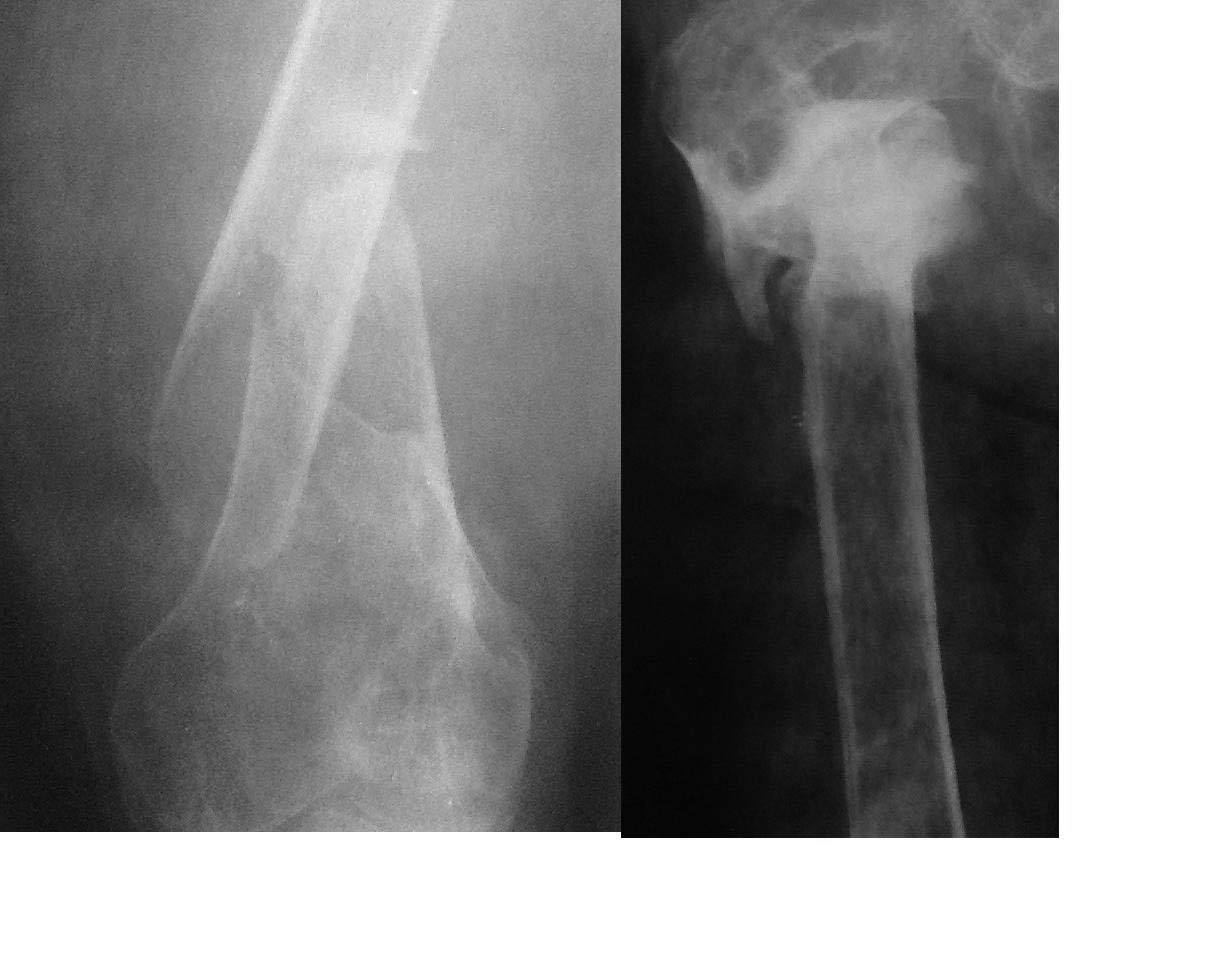

Псевдоартроз правой бедренной кости в н/3 |

Пациент 52 года обратился с диагнозом псевдоартроз правой бедренной кости в нижней трети. Из анамнеза в 1986 году политравма в результате ДТП: таз, кости голени, проксимальное бедро справа (обращает на себя особое внимание в силу неправильной консолидации см. снимки). В 2010 бытовая травма: перелом диафиза правого бедра в н/3. Консервативное лечение на скелетном вытяжении около 3-х месяцев с формированием ложного сустава и фиброзного анкилоза правого коленного сустава. Лечился в спице-стержневом аппарате внешней фиксации, последний был демонтирован в связи с формированием спицевого остеомиелита. На данный момент кожный покров чистый, больной передвигается на костылях без опоры на конечность. Закрытый интромедуллярный остеосинтез по классическим методикам кажется проблематичным в силу невозможности сформировать точки входа (анкилоз коленного сустава при ретроградном, неправильно сросшийся перелом проксимального отдела бедра при антеградном остеосинтезе). В итоге склоняемся к остеосинтезу пластиной с костной пластикой. Однако, учитывая низкое качество кости, остеомиелит в анамнезе, открытые вмешательства не кажутся оптимальными. Хотелось бы услышать альтернативные варианты/предложения по лечению данного пациента.